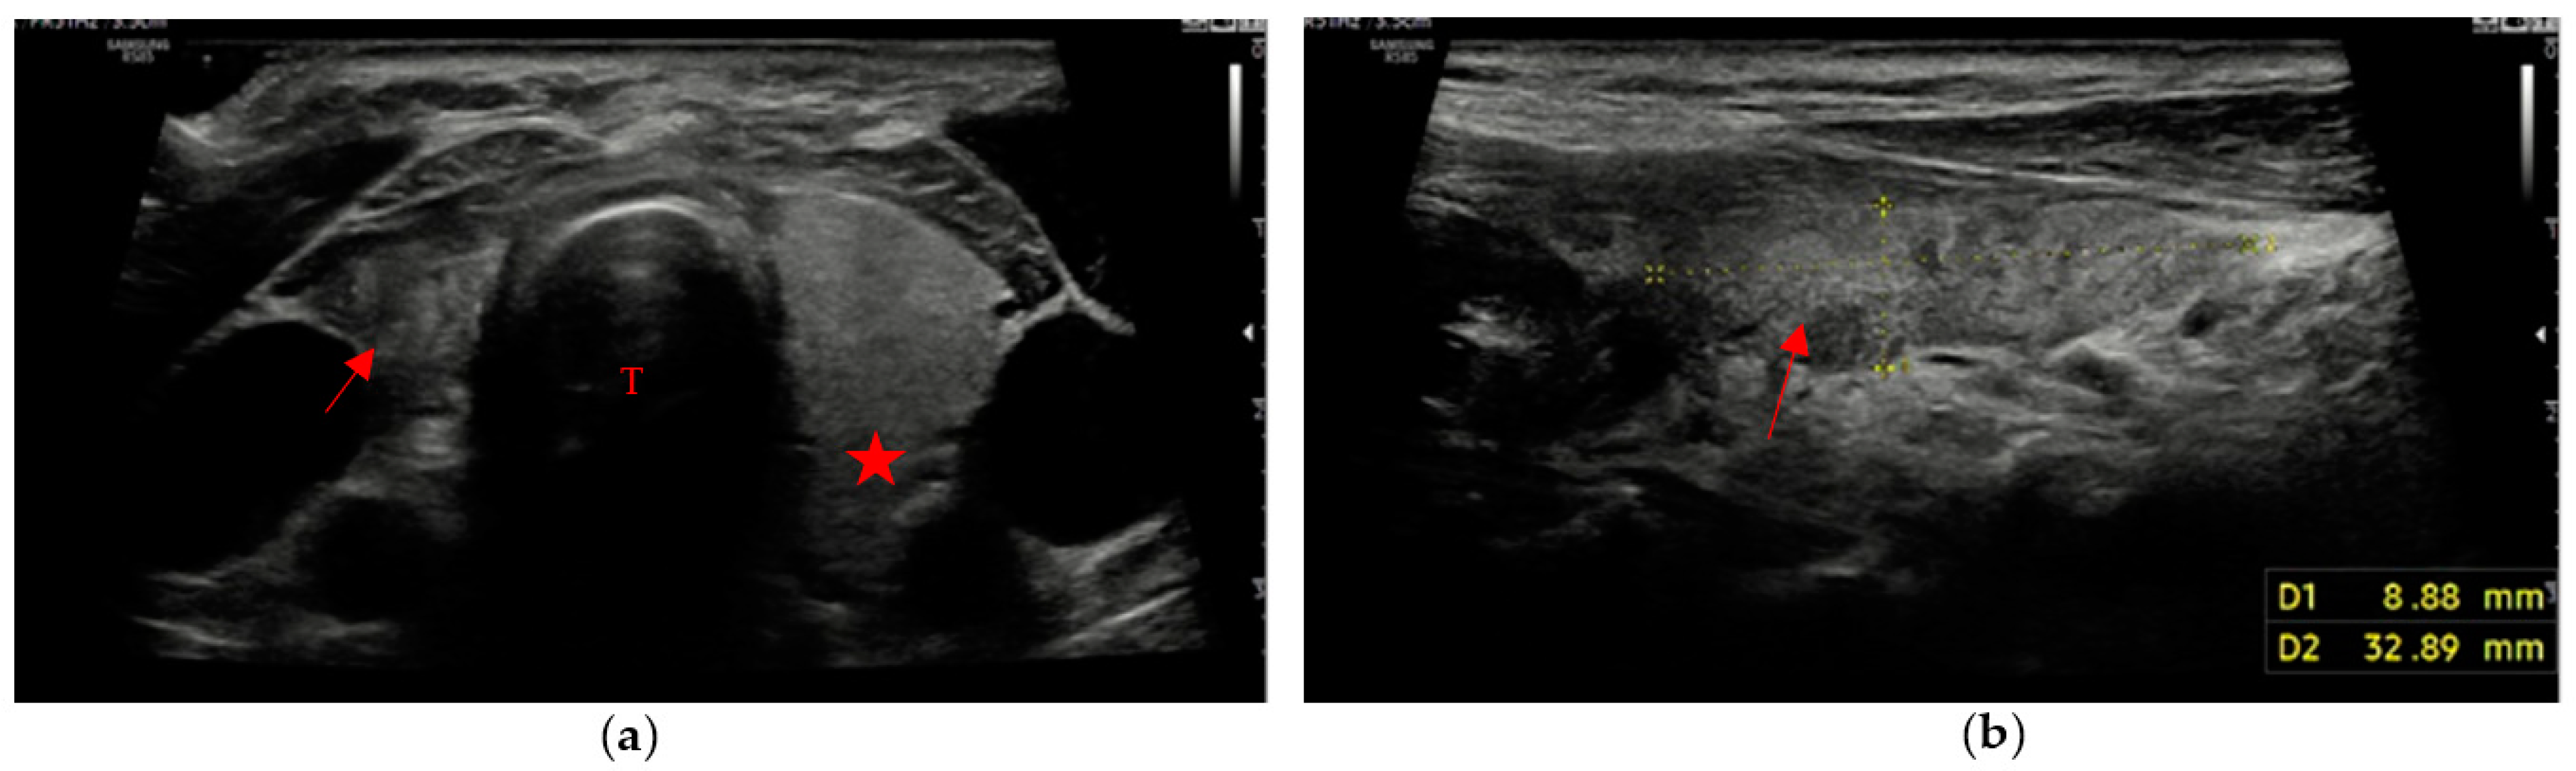

The remaining 3 patients (8% of patients with evidence of residual swab) showed different patterns, with different combinations of margins and ecogenicity. In our experience, we have also found different swab shapes, but the most common are ovoid or pseudo-ovoid shapes; these are the most frequent and most “thyroid-like” shape, and are caused when the remnant has completely obliterated the thyroid space that reproduces the native thyroid gland shape. This form is often associated with the mildly hypoechoic pattern with ill-defined margins (Figure 3a,b).

Figure 3. “Thyroid-like” shape of the swab (red arrow) in a right hemithyroidectomy (the native gland, pointed out by a red star, is still visible on the left). Trachea (T). (a) Axial view; (b) Longitudinal view.